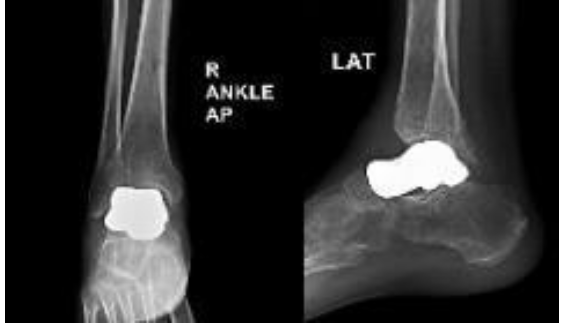

In view of progressive talar collapse and failure of the initial fixation, the patient was admitted for implant removal and definitive surgical management. The patient underwent right talar replacement using a custom-made 3D-printed titanium implant manufactured by Bonetech Medysys, following detailed pre-operative planning. High-resolution computed tomography imaging of the contralateral healthy ankle was used to generate a three-dimensional model for the fabrication of patient-specific talar prosthesis. Magnetic resonance imaging was also performed to assess cartilage thickness, which aided implant size planning. Multiple sizes of the implant were prepared. Intraoperatively, the non-viable talus affected by AVN was excised, and the ankle joint was fully exposed. All the bony fragments of talus were removed. The posterior capsule was released to get an adequate range of movement, and the appropriately sized custom implant was positioned to restore joint alignment and function. The procedure was completed successfully, with stable intraoperative joint movement, and the patient was transferred to post-operative care in a hemodynamically stable condition. Postoperatively, a below-knee slab was applied, and the patient was kept on non-weight bearing for 1 month. At the 4-month follow-up, the patient reported an improvement in pain and function. Hindfoot varus and cavus were corrected, and gait improved significantly. Both VAS and AOFAS scores showed improvement at short-term follow-up. Post-operative X-rays taken at 4-week and 4-month follow-up showed that the implant was in a stable condition (Fig. 3 and 4).

Figure 3: Post-operative anteroposterior and lateral views at 4-week follow-up showing a well-positioned custom 3D-printed talar implant with restored ankle alignment and no evidence of early subsidence.